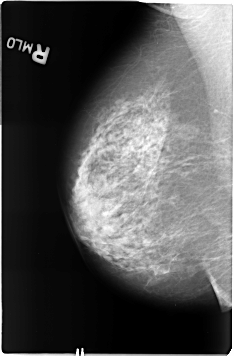

Digital Database for Screening Mammography

Volume: benign_04 Case: B-3361-1

B_3361_1.RIGHT_MLO

RIGHT_MLO LINES 4624 PIXELS_PER_LINE 3032 BITS_PER_PIXEL 12 RESOLUTION 50 NON_OVERLAY